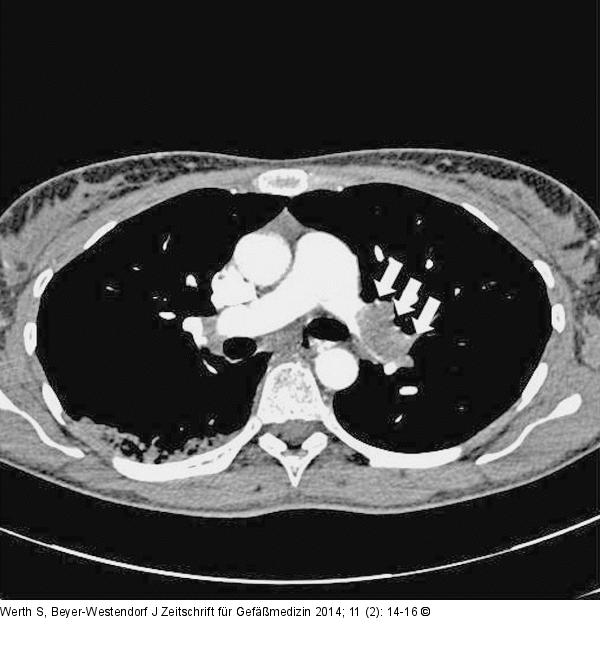

Abbildung 1: CT-Angiographie CT-Angiographie mit bipulmonaler zentraler Lungenarterienembolie, als Kontrastmittel-Aussparung unter Betonung des Hauptstammes der linken Pulmonalarterie (Pfeile) |

CT-Angiographie mit bipulmonaler zentraler Lungenarterienembolie, als Kontrastmittel-Aussparung unter Betonung des Hauptstammes der linken Pulmonalarterie (Pfeile) |